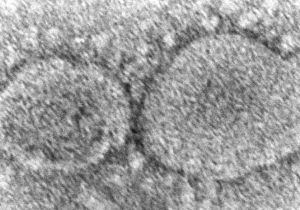

क्या चीन के वुहान लैब से लीक हुआ कोरोना वायरस? अभी भी बना रहस्य

2 Mar, 2023 08:58 PM IST | ASIAVARTANEWS.COMनई दिल्ली व्हाइट हाउस ने कहा है कि इस बात का कोई निश्चित निष्कर्ष नहीं है...